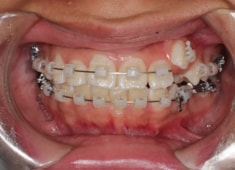

治療開始時